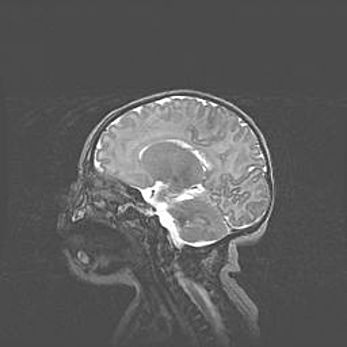

Аномалия Денди-Уокера. Признаки гипоплазии мозолистого тела.

Возраст: 5 месяцев 3 дня

Вес: 5550 г

Пол: мужской

Окружность головы: 39 см

Срок гестации: 40 недель

Аномалия Денди-Уокера – это порок развития головного мозга, для которого характерна триада симптомов: гипотрофия или аплазия червя мозжечка и/или полушарий мозжечка, расширение четвёртого желудочка с формированием ликворной кисты задней черепной ямки, гипертензионная гидроцефалия различной степени.

Гипоплазия мозолистого тела относится к дефектам внутриутробного этапа развития мозговой ткани, возникающим в процессе закладки структур головного мозга, что происходит на начальных этапах развития эмбриона.